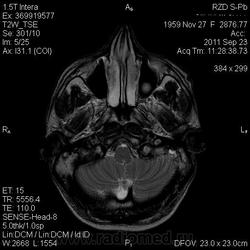

Похоже на метастазы

Тоже за метастазы. Достаточно большой отек при небольших образований.

я тоже думаю про метастазы, но уж сильно много сомнений.... и как будто бы капсула в субтенториальном очаге на нативных снимках, и на кт вроде бы как на абсцесс похоже.....

В данном случае был дифф. диагноз с абсцессом головного мозга (вариант сепсиса тоже рассматривался), т.к у пациента была и лихорадка и ЛОР-патология; но учитывая количество очагов (если смотреть все МР-снимки, выявляется ещё 2 мелких очага в коре) не исключено наличие метастазов + периферических характер накопления- можно предполагать и то и другое.

Кольцевидное накопление - может легкие?

Это абсцессы. Равномерной толщины стенки, ровные контуры. На Т2 содержимое полостей имеет средний уровень сигнала - для абсцессов это характерно. Для дифференциации нужно было сделать DWI, тогда гной имел бы повышенный уровень сигнала. Хороший аппарат, почему не сделали?

Метастазы при отсутствующем онкоанамнезе в среднем возрасте бывают все же редко. К тому же лихорадка, лейкопения как проявление снижения иммунитета.

пришла положительная ф50 и ликвор с токсоплазмой

это к вопросу корона-эффекта (кольцевидного накопления), что встрчается при многих заболеваниях и не является специфичным.

"мнрогоочаговое поражение головного мозга супра/субтенториальной локализации. Дифференциальный диагноз с инфекционным, метастатическим поражением головного мозга"